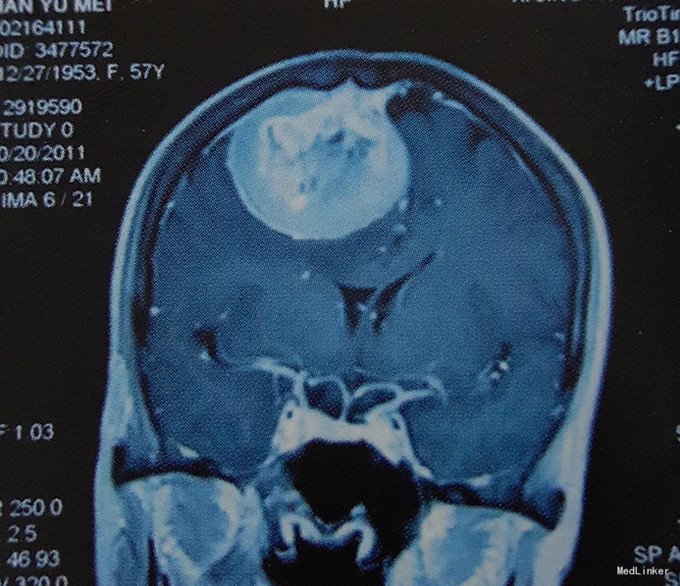

患者女,57岁,主因”头痛、头晕伴左侧肢体无力半月“入院。 患者于入院前半个月无明显诱因出现头痛、头晕,伴左侧肢体无力,行走时步态不稳,遂至当地医院就诊。无癫痫病史,无其他特殊不适,既往无特殊病史。

查体:心肺腹体检无明显异常,生命体征平稳,左上肢及左下肢肌力IV级,右侧肢体肌力V级,四肢肌张力正常,其他神经系统检查无明显异常。 颅脑MRI增强扫描:右顶部中央沟区矢状窦-镰旁巨大占位,强化效应明显,质地均匀边界清,中线及周围脑组织明显受压。

诊断:右顶中央沟区矢状窦-镰旁巨大占位。 治疗:入院后在全麻下行开颅探查右顶中央沟区矢状窦-镰旁巨大脑膜瘤切除术。 术后病理结果回报示:右顶矢状窦旁-镰旁纤维型脑膜瘤(WHO I级)。